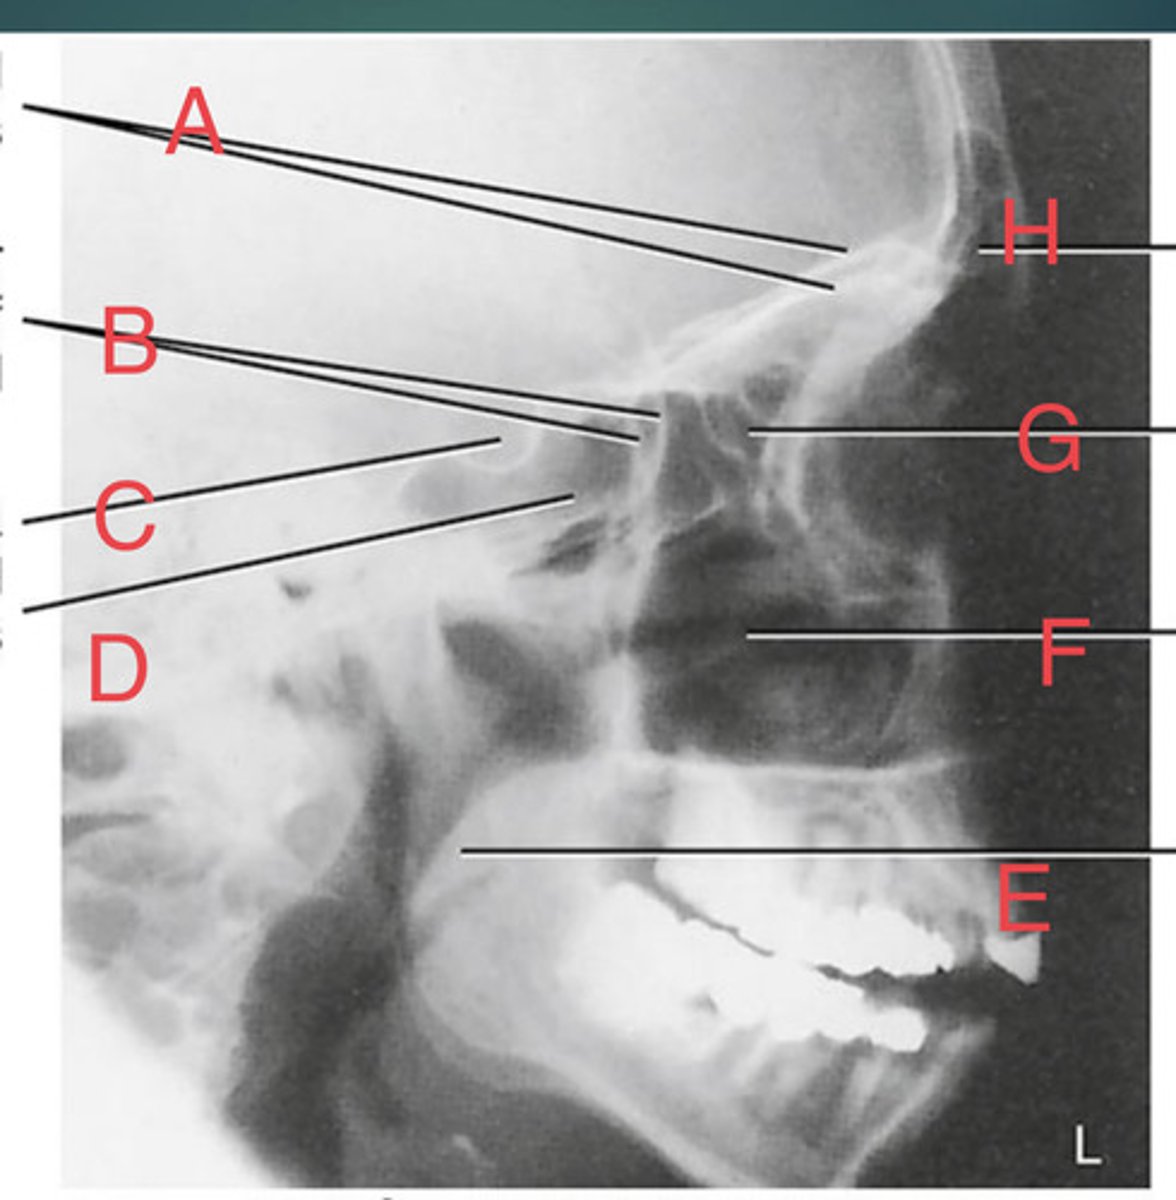

PA Caldwell Sinuses

What position?

frontal sinus of the frontal bone

A.

R. ethmoid sinus of the ethmoid bone

B.

crista galli of ethmoid bone

C.

L superior orbital fissure of the sphenoid

D.